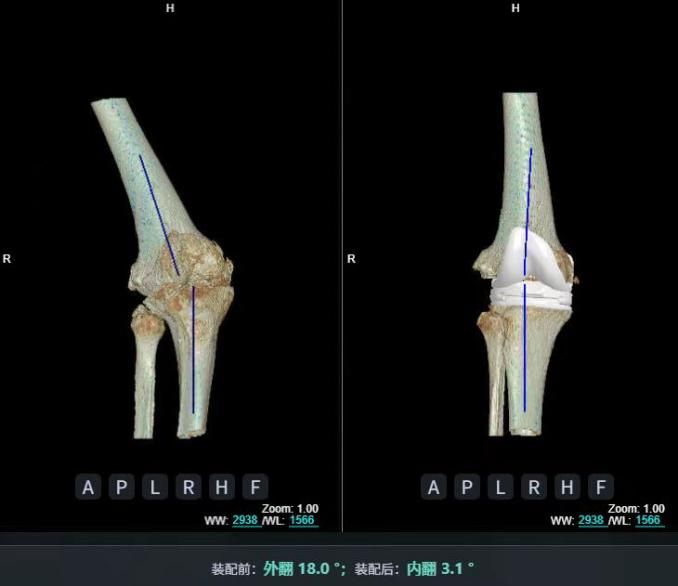

4.2 APTT-HTO脛骨高位截骨術(shù)

2025年7月,貴州醫(yī)科大學(xué)附屬醫(yī)院骨科團(tuán)隊原創(chuàng)研發(fā)的腘肌前結(jié)節(jié)中脛骨高位截骨保膝術(shù)(Anterior Popliteus Transtibial Tuberosity-High Tibial Osteotomy, APTT-HTO)及其提出的脛骨結(jié)節(jié)分區(qū)與腘肌保護(hù)理論,登上了國際頂尖學(xué)術(shù)舞臺。該成果在全球最具影響力的專業(yè)會議之一——日本骨科協(xié)會第98屆年會上進(jìn)行了兩次學(xué)術(shù)發(fā)言。[8]

該手術(shù)具有經(jīng)皮微創(chuàng)、保留原生膝關(guān)節(jié)結(jié)構(gòu)、符合階梯治療原則等優(yōu)勢,通過調(diào)整下肢力線可促進(jìn)部分軟骨再生,術(shù)后關(guān)節(jié)功能接近正常(如下蹲、爬山),患者還能從事中重體力勞動。相比其他術(shù)式,其有效規(guī)避了髕骨低位、血管損傷、合頁骨折等潛在并發(fā)癥。

目前,APTT-HTO技術(shù)已成功應(yīng)用于千余名患者,幫助保留自身膝關(guān)節(jié)。此類保膝手術(shù)適用于單間室膝關(guān)節(jié)炎患者(如 “羅圈腿”),核心是通過調(diào)整力線糾正畸形,減輕磨損間室壓力、發(fā)揮健康間室作用,延長膝關(guān)節(jié)壽命。若出現(xiàn)膝關(guān)節(jié)疼痛、保守治療無效且X線顯示關(guān)節(jié)間隙部分狹窄,建議及時就醫(yī)評估是否適合手術(shù)。